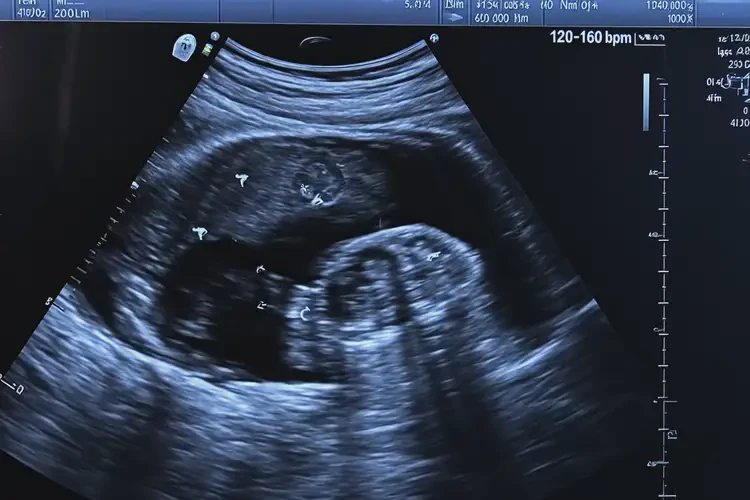

懷孕七個(gè)多月時(shí),胎心率在160次/分鐘是正常的。胎心率是指胎兒心臟每分鐘跳動(dòng)的次數(shù),通常在120-160次/分鐘之間被認(rèn)為是正常范圍。胎心率可能會(huì)受到多種因素的影響,包括胎兒的活動(dòng)水平、母親的情緒和身體狀況等。單次胎心率測(cè)量結(jié)果并不能完全反映胎兒的健康狀況。

胎心率的正常范圍是120-160次/分鐘。在這個(gè)范圍內(nèi),胎兒的心臟功能是正常的。

懷孕七個(gè)多月胎心160多寶寶還能要嗎(圖1)